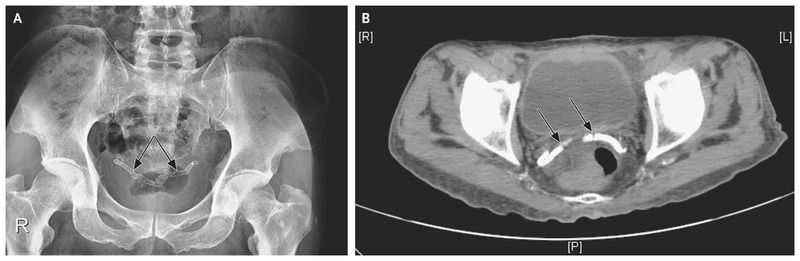

Although no hydronephrosis or radiopaque kidney stones were present, bilateral tubular calcification of the vasa deferentia was incidentally noted on a plain radiograph (Panel A, arrows) and on an axial section of a computed tomographic image of the pelvis, performed without the administration of contrast material (Panel B, arrows).